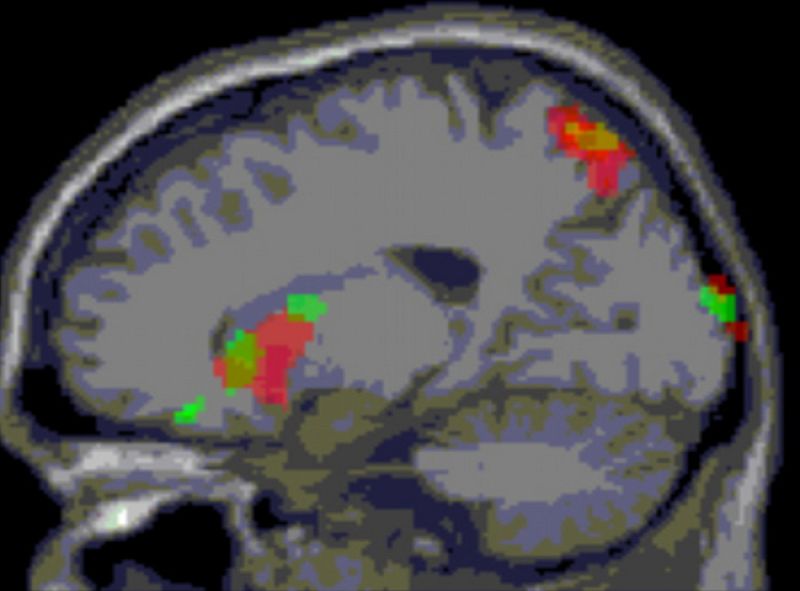

Eso es lo que les pasa a algunas personas que han sufrido daño cerebral por un golpe en la cabeza o un ictus. Los casos conocidos son pocos y ni siquiera hay un diagnóstico claro. Por eso, para poder describir el trastorno, están realizando un estudio en el Centro Estatal de Daño Cerebral Adquirido.